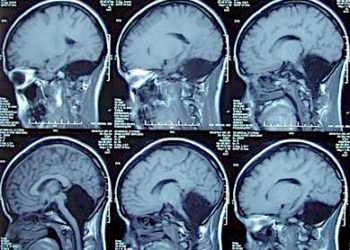

De vez em quando, imagens como esta circulam e viralizam na internet. Talvez porque as pessoas não imaginassem que a...

Os cérebros de quatro senhoras com idades entre 80 e 82 anos que morreram em São Paulo contam um pouco...